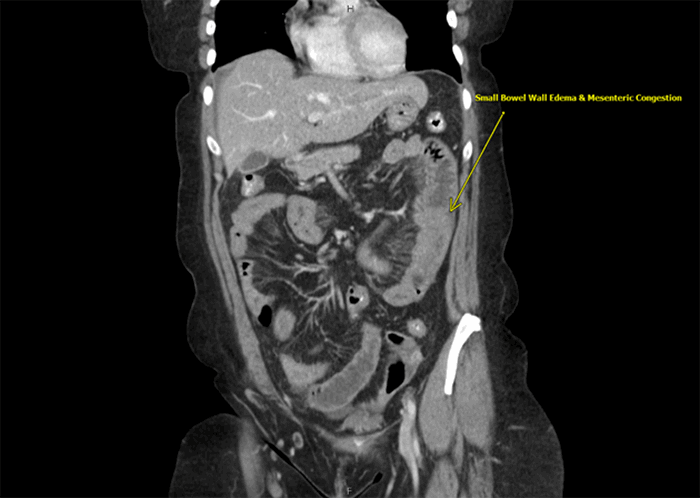

The patient is a 56-year old female with a body mass index (BMI) of 33.2 kg/m2, Type II diabetes mellitus, hypertension, asthma, and previous abdominal surgery, including appendectomy and hysterectomy. She presented to the emergency room in early May 2020 with severe periumbilical pain, rated 10/10, and nausea and vomiting, which had begun the evening prior. On physical examination, she appeared uncomfortable. She had lower and left-sided abdominal tenderness with guarding. At presentation, the patient denied fever, chills, cough, or shortness of breath. Initially, she was tachycardic (pulse rate 108) but was normotensive and had normal oxygen saturation on room air. Laboratory values were normal except for leukocytosis (white blood cell count 12.2 × 1000/μL) and elevated blood glucose. Lactate was normal at 1.1 mmol/L. Computed tomography (CT) scan showed bowel wall thickening involving large portions of the jejunum and ileum with mesenteric congestion and a moderate amount of free fluid in the pelvis (Figure 1). There was no sign of thromboembolism in the main mesenteric vessels, but there was a suggestion of pneumatosis in the left mid-abdomen (Figure 2). Peripheral patchy ground-glass opacities were seen in the visualized lower portions of both lungs, suggestive of atypical or viral pneumonia.

Figure 1. Coronal CT of Abdomen and Pelvis with Intravenous Contrast. Published with Permission

Multiple loops of small bowel demonstrated severe bowel wall thickening with mesenteric congestion and edema.